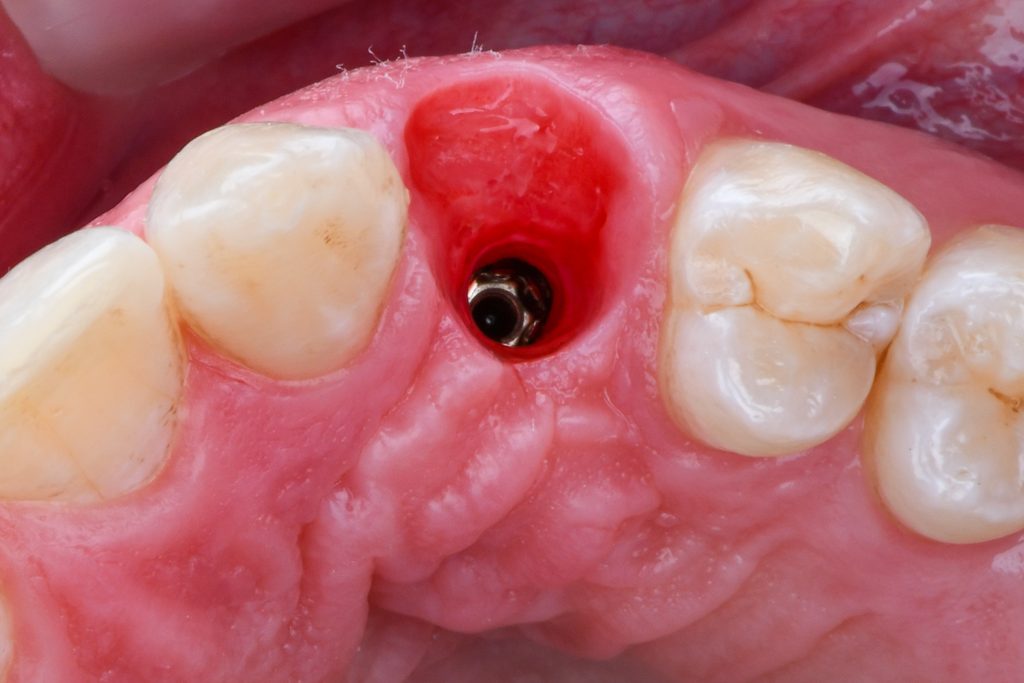

A 24-year-old female patient referred by an orthodontist who resolved the unilateral agenesis of the left upper lateral incisor by mesializing the left upper cuspid and shifting the gap in between teeth 23 and 25. After confirming the free bone corridor between the roots of the cuspid and the first bicuspid, a Straumann BLX RB implant (3.75 mm) was inserted and thin soft tissue buccally augmented with tuberosity connective graft. A sliding island flap on the palatal side relieved tension while suturing both sides of the mucosa. Three months later, the ortho appliance was removed and a temporary crown (Cerasmart) was delivered. All teeth were whitened and after four-month-period, an all-ceramic crown (Katana) was made and fixed. The patient denied and reshaping of the tooth 23. In 3 years, the situation is sthbilized however the prognosis of the tissue covering the tooth 23 is doubtful. Prosthetic part of the treatment done by a.krugova

emergence profile trained by a temporary crown